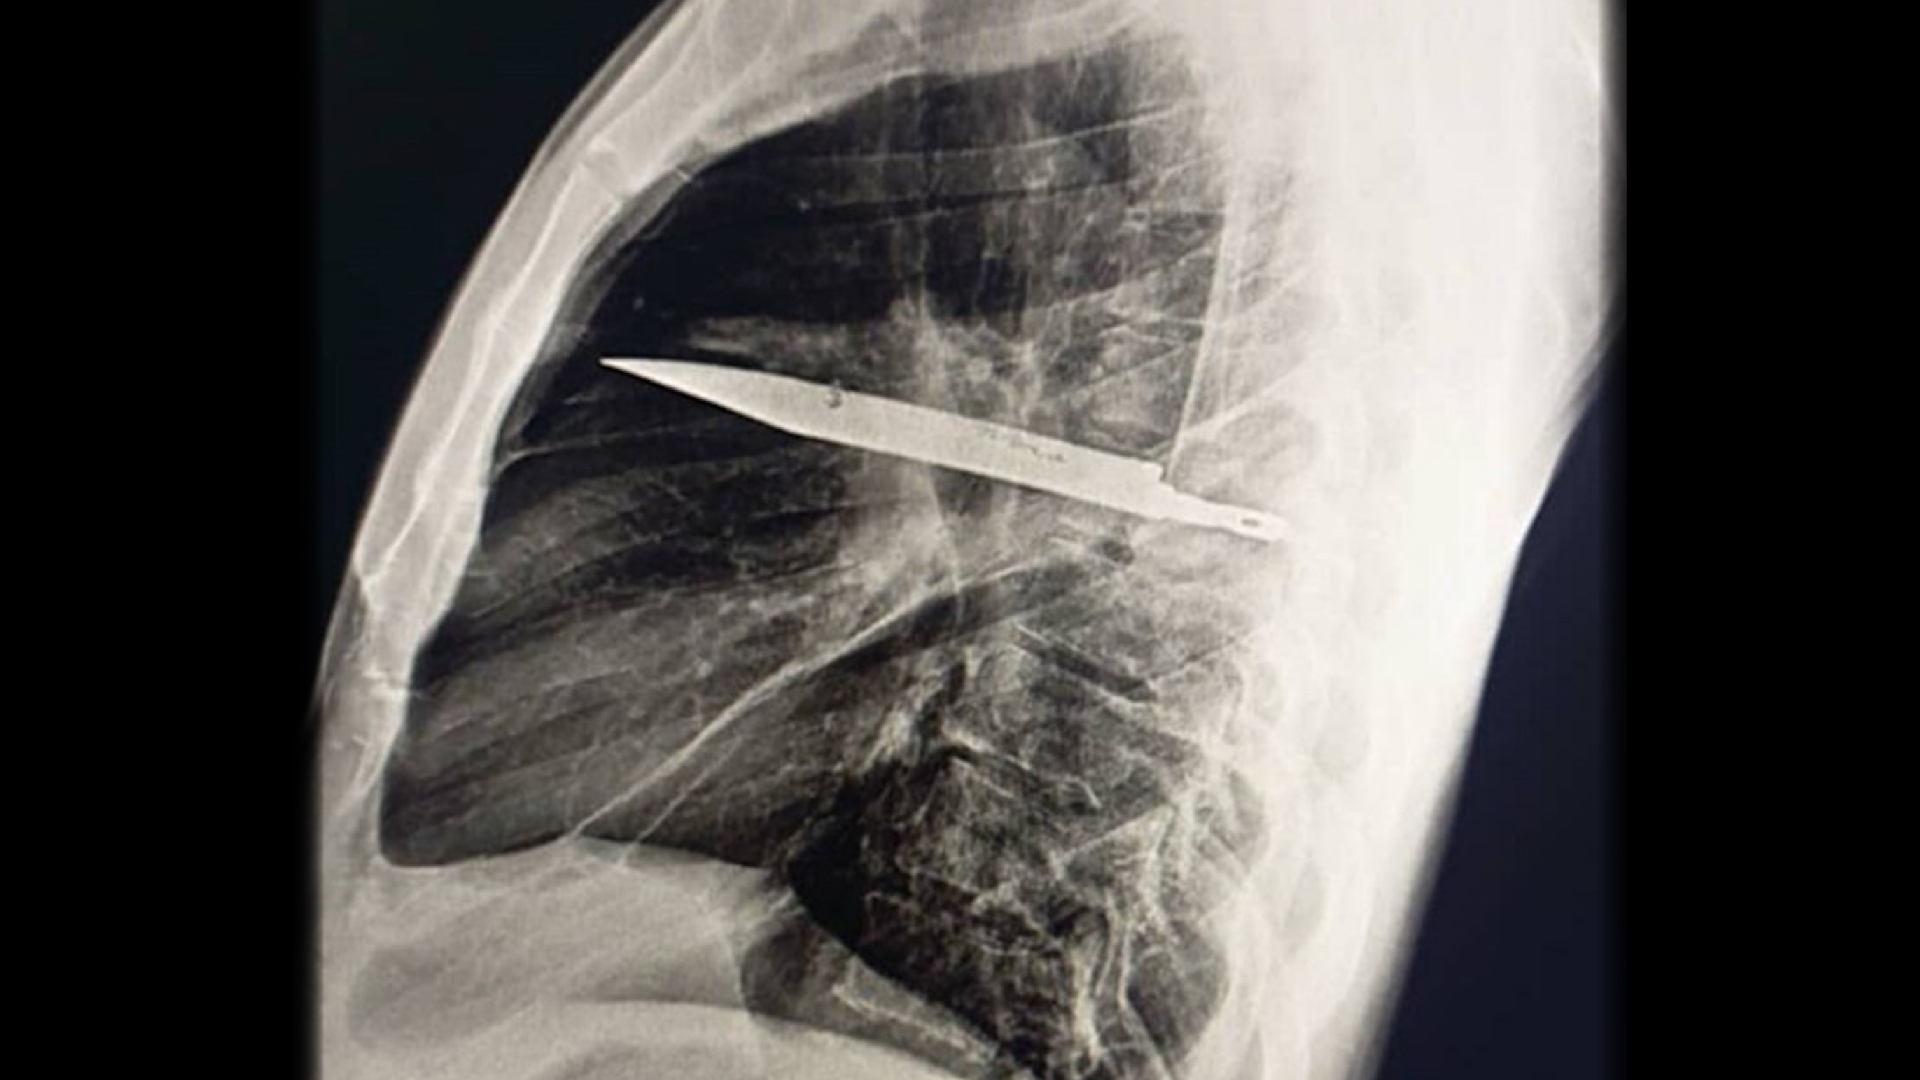

Diagnosis: X-rays revealed a large metallic knife blade trapped inside the male’s chest cavity. This hollow chamber, also known as the thoracic cavity, resides above the abdomen and contains the heart and lungs. The blade, which extended from behind the thorax forward, entered the man’s back, near the right or scapula.

The knife blade was clogged there after sliding between the fifth and sixth ribs on the patient’s back, and the tip of the knife was placed between the third and fourth ribs on the front of the thoracic cage. CT scans showed healed fractures in the shoulder blades and several ribs. A layer of pus and dead or dying tissue surrounded the knife blade.